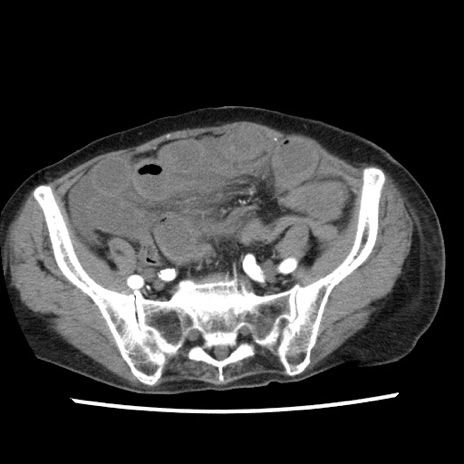

症例1(横断像)

【症例】80歳代女性

【主訴】腹痛

【現病歴】8時間前から腹痛あり来院。

【既往歴】糖尿病、脂質異常症、子宮体癌にて子宮全摘術

【身体所見】意識清明・会話良好だが腹痛で苦悶様、全腹部にわたって反跳痛と圧痛あり

【データ】WBC 13600、CRP 0.14、LDH 224、CK 90